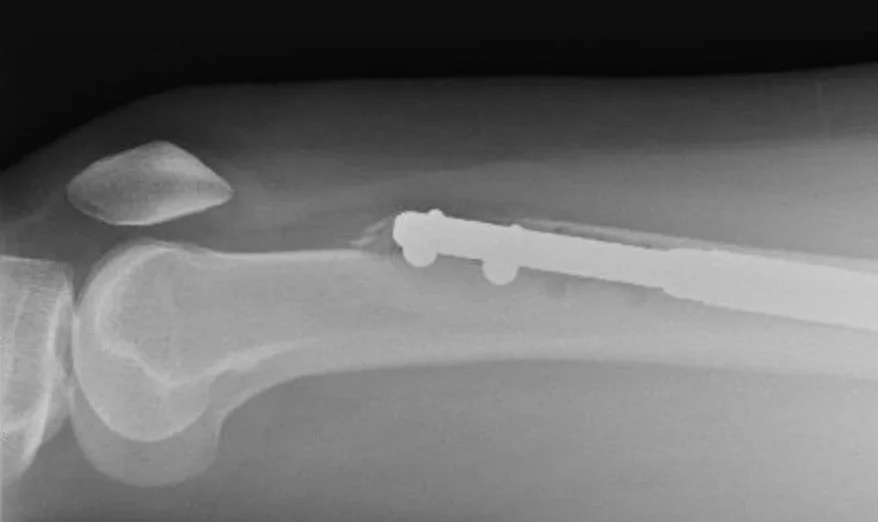

При цій процедурі можна очікувати певного болю. Під час операції кістки ноги розламують і всередину вставляють металевий стрижень.

Металеві стрижні поступово висуваються, збільшуючи свою довжину та розтягуючи дві половини кістки. Цей процес має збільшити зріст пацієнта. Зламані кістки повинні поступово зрощуватися, щоб заповнити проміжок між ними.

Елейн пішла на рентген, який підтвердив її побоювання. Цвях у її лівій нозі пробив стегнову кістку — найміцнішу кістку в людському тілі. Вона була збентежена, але доктор Гіше її заспокоїв.

Через шість тижнів рентген показав тривожну відсутність зростання. Її стегнова кістка складалася по суті з двох шматків, скріплених металевим стрижнем.